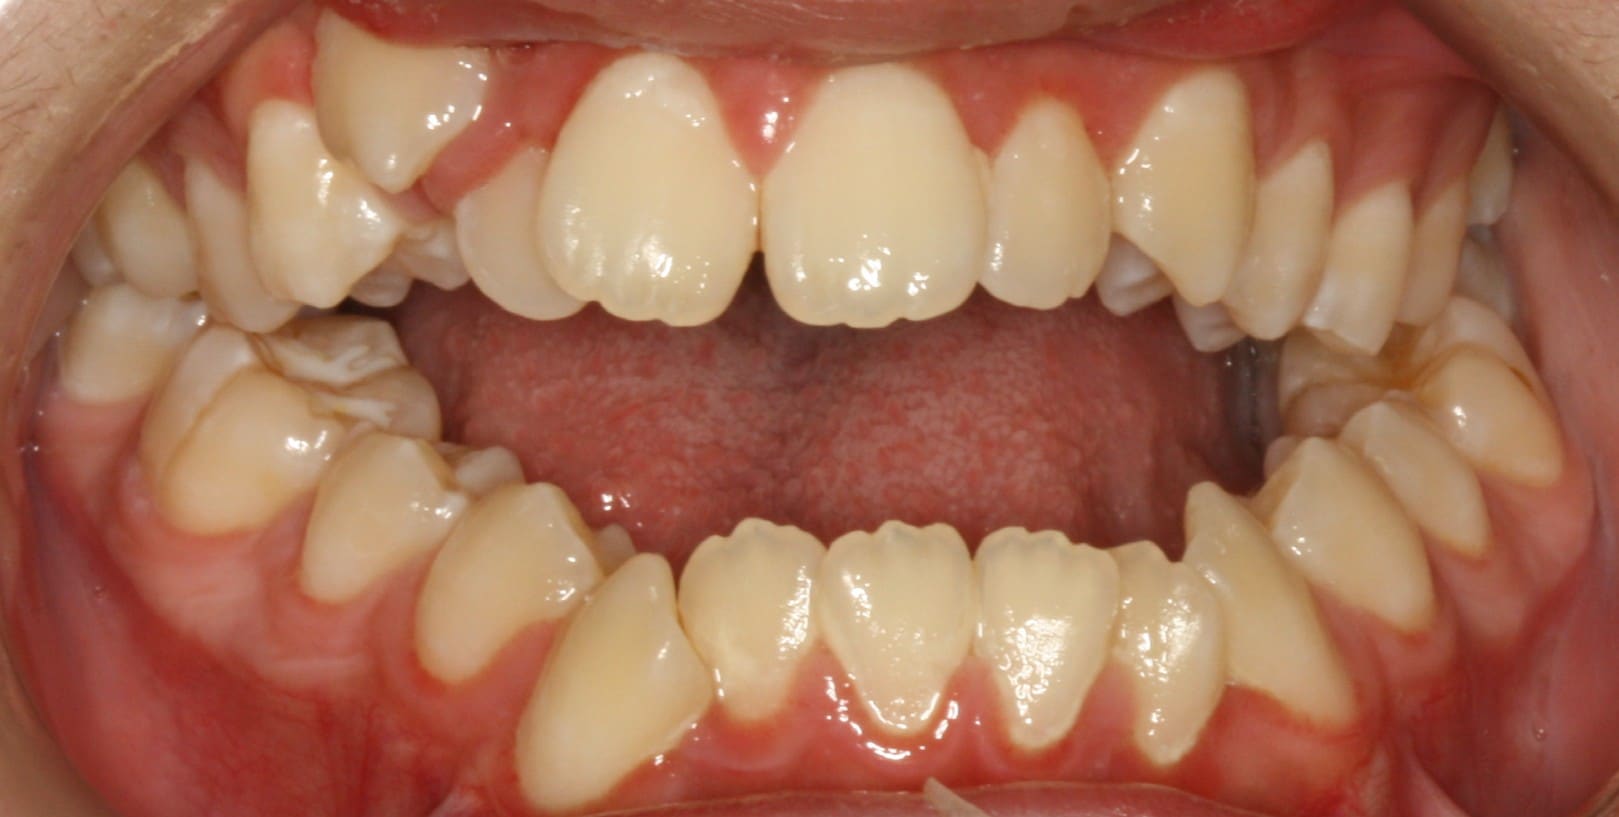

Adult patient treated with Invisalign aligners